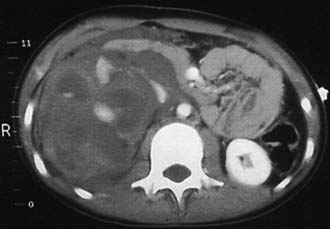

A 3-phase spiral CT scan should be performed to evaluate the kidneys, ureters, and bladder. The delayed images are important to detect renal extravasation of blood or urine. Prompt function of both kidneys without extravasation usually excludes significant renal injury. Renal injuries are classified according to the grading scale presented in Table 540-1. Minor renal injuries are most common; these include contusion of the renal parenchyma and shallow cortical lacerations not involving the collecting system. Major renal injuries include deep lacerations involving the collecting system, the shattered kidney, and renal pedicle injuries (Fig. 540-1). Complete absence of function of 1 kidney without contralateral compensatory hypertrophy (indicating congenital absence) should be regarded as an indication of major injury to the renal pedicle. Renal angiography, once used for further evaluation of renal injuries, particularly if a renal pedicle injury is suspected, now is rarely used because such patients are often hemodynamically unstable, and management is not significantly affected by the findings. In some cases, a pre-existing renal anomaly is demonstrated on the study. A ruptured ureteropelvic junction obstruction may be apparent if the kidney is intact but the distal ureter is not visualized.

Figure 540-1 CT scan of a girl who sustained major renal injury when she fell off a bicycle. The scan demonstrates a ruptured right kidney with urinary extravasation.